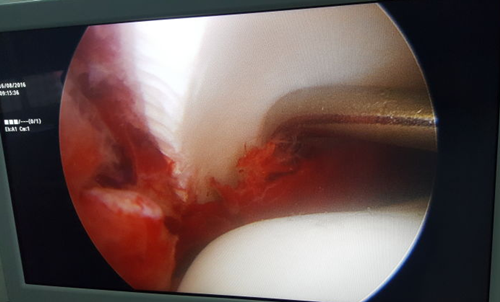

图为术中操作

境下用探钩清理骨折断端软组织及血凝块

关节镜技术是近年来骨折领域的一大进展,目前临床医学院/附属医院以膝、肩关节镜为主。通过关节镜技术可在直视下观察骨折断端复位和关节面情况,很大程度上弥补了开放手术观察视野不足和切口较大的缺陷,此外还便于术中检查关节腔内有无游离的小骨折块或者小的游离体。踝关节镜手术具有创伤小(切口仅为0.5cm)、出血少、康复快、并发症少及有利于患者早期康复训练等优点,成为运动医学领域的一个重要分支。